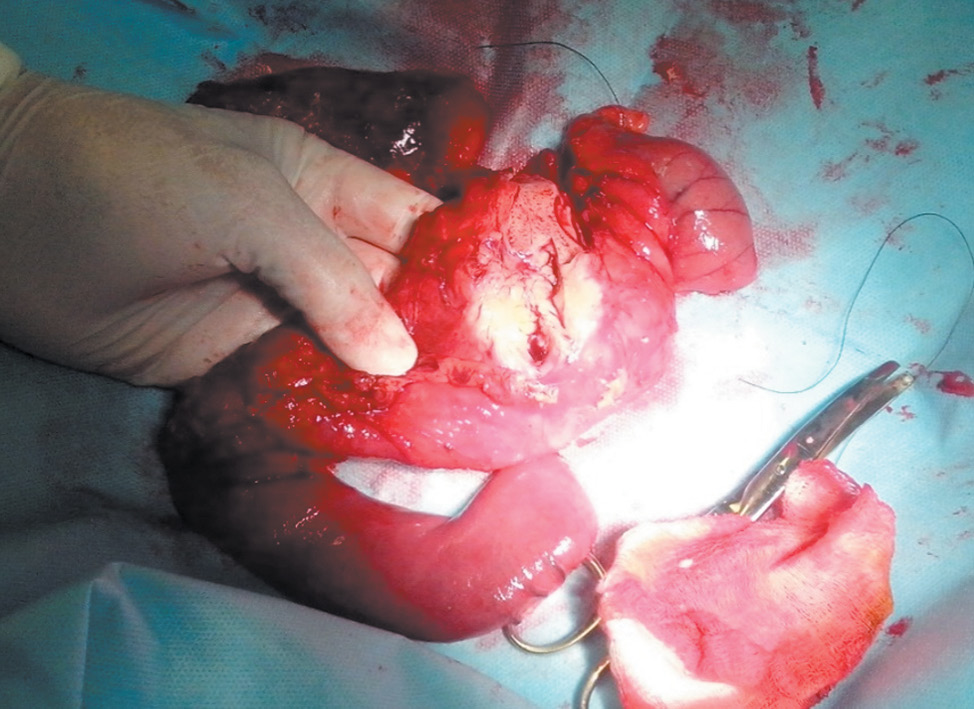

An emergency laparotomy was performed on the patient. During the revision, a dense tuberous mass up to 3–4 cm in diameter was palpated in the projection of the pancreatic head and the duodenal lumen. The surgery was performed at night, without the possibility of an urgent histological examination. Therefore, the decision on the amount of intervention was made based on clinical data and the results of previous studies. The tumor was considered resectable. The patient underwent a gastropancreatoduodenal resection, as shown in the photo of the organ complex in Fig. 3.

Fig. 3. Specimen section: whitish dense tumor in the head of the pancreas

Рис. 3. Макропрепарат. На разрезе опухоль в головке поджелудочной железы